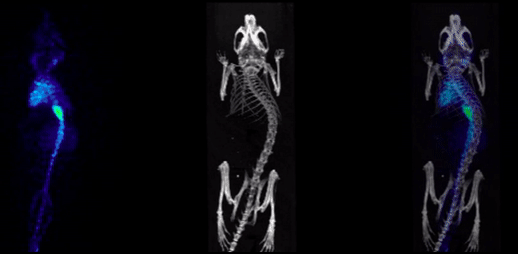

2、CT imaging combined with SPECT

SPECT/CT combination images, bone imaging of mice: 99mTc-HDP, 94.35MBq (2.55mCi) @start acquisition, acquisition time of 60min.

和SPECT融合.png